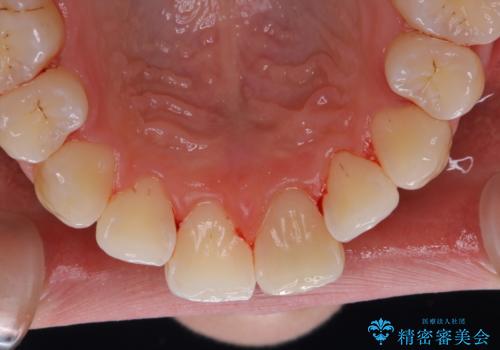

1年ぶりにPMTCで歯の着色落とし

- しばらく歯科医院へ行けなかったため、しっかり着色や汚れを落として欲しいとのことで来院されました。全体的に着色や歯石が付着していたためPMTC60分コースを行いました。

ご自身でのセルフケアだけで着色を落とそうとすると、逆に歯を傷つけてしまったり、的確に汚れを取りきれないことがあります。また、日常生活で着色しやすい飲食物を避けたりすることはストレスに感じてしまったり、あまり現実的ではありません。

定期的に歯科医院にて、適切な処置を行うことで、健康的なお口の状態を維持することにつながります。